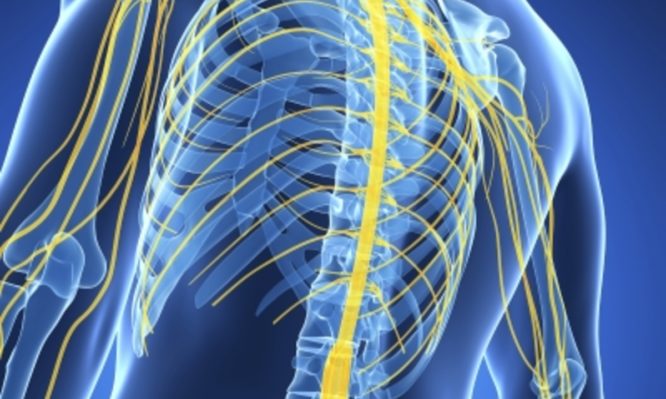

Εκατοντάδες ασθενείς με κακώσεις, οστεοαρθρίτιδα, τενοντίτιδα ή κήλη μεσοσπονδύλιου δίσκου που υποφέρουν καθημερινά από πόνους και δυσκολεύονται να πραγματοποιήσουν...